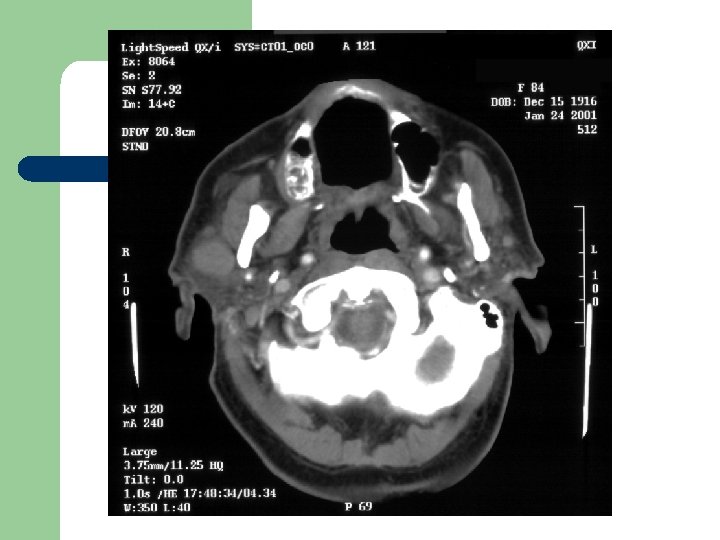

Radiological Evaluation l CT Scan and MRI: To determine the extension of the disease.